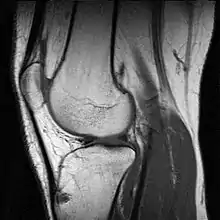

L'imagerie par résonance magnétique (IRM) permet d'observer tous les éléments de l'articulation. Elle est souvent réalisée en cas de rupture des ligaments